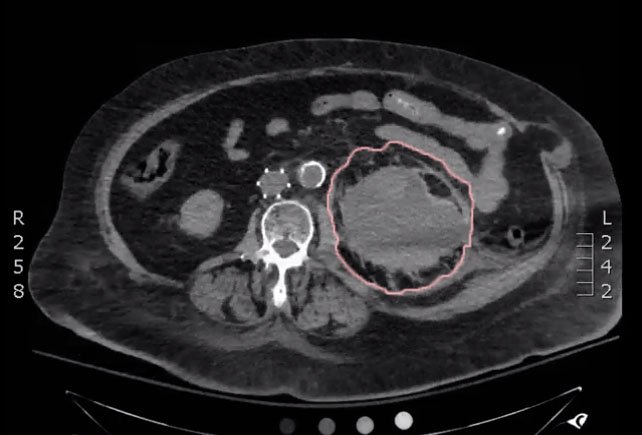

Bedside ultrasound was performed and demonstrated a hypoechoic area within the left kidney (images not shown). The non-contrast computed tomography (CT) of the abdomen and pelvis shows a significantly enlarged left kidney and a region of high-attenuation encapsulating the left kidney, concerning for acute hemorrhage.